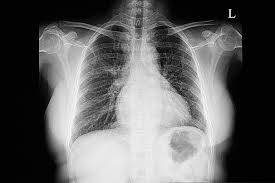

تشخيص تضخم القلب كان من الضروري إجراء أشعة سينية على الصدر لكل من الرئتين والقلب. للتحقق من وجود تشوهات في القلب قد يفكر الطبيب في استخدام فحص القلب باستخدام جهاز صدى عالي التردد. (مخطط صدى القلب) لمعرفة خصائص حجرات القلب. وظيفة عضلة القلب وصمامات القلب ضغط القلب بما في ذلك مخطط كهربية القلب. مخطط كهربية القلب (مخطط كهربية القلب) للتحقق من عدم انتظام ضربات القلب بالإضافة إلى ذلك، يمكن إجراء اختبارات الدم، واختبارات التصوير بالرنين المغناطيسي ، والأشعة المقطعية ، وخزعات القلب، اعتمادًا على نصيحة الطبيب. للمساعدة في إجراء التشخيص الصحيح يؤدي إلى العلاج المناسب